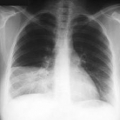

Этот вид пневмонии характеризуется поражением одной доли лёгкого, целого лёгкого или даже обоих лёгких. Чем больше объём поражения — тем тяжелее протекает процесс. Вызывается крупозная пневмония пневмококком. Кроме повреждения ткани легкого бактерия, выделяя токсичные для человека вещества, действует на весь организм – сильно повышается температура, появляется озноб.